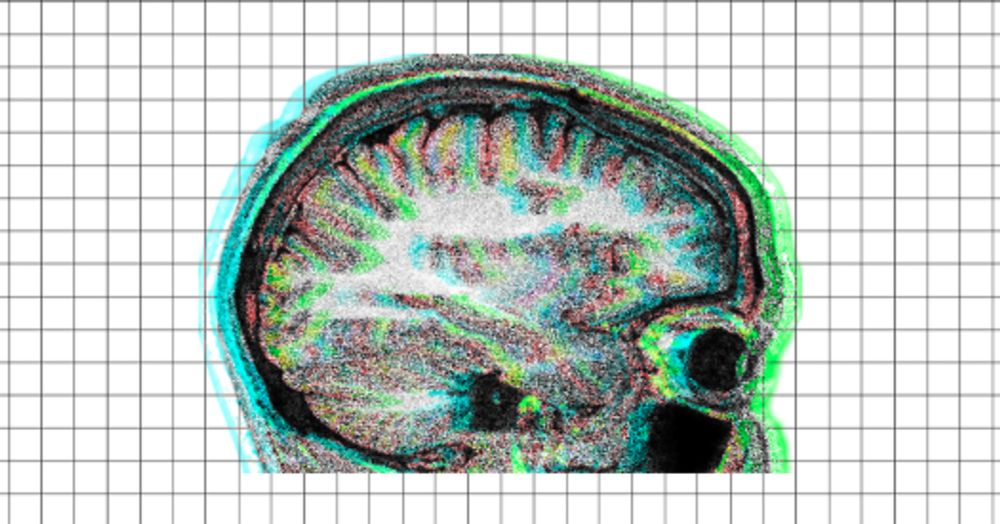

#science #scientificmethod #fmri

Authors retract Science paper on controversial fMRI method

Several MRI artifacts contribute to the neuronal activity signal picked up by the method, according to a preprint the authors posted this month.